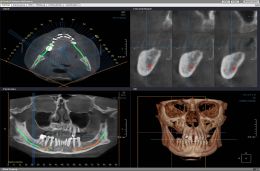

TC Cone Beam 3d

Figura 19

La TC cone beam dentale aperta utilizza un fascio di radiazioni a cono collimato su un rivelatore per raggi x; il sistema tubo rivelatore compie una rotazione di 360° attorno alla testa del paziente eseguendo una serie di radiogrammi digitali secondo angoli prestabiliti; dalla ricostruzione primaria si ottengono le immagini assiali dello spessore prescelto e, nella fase successiva si visualizzano le ricostruzioni secondarie (MPR, volumetriche e di superficie); l’apparecchio consente di effettuare misurazioni, di evidenziare il canale mandibolare, la simulazione di impianti, l’output in formato file Dicom 3.

Pertanto utile e proponibile l’utilizzo dei Minimpianti in molteplici casi clinici in presenza di atrofie di vario grado e l’utilizzo della nuova Diagnostica Radiologica per immagini Tc Cone Beam 3d, per un alta predicibilità pre - implantare, al fine di ottimizzare ogni intervento, e di poter avere ogni massimo rispetto delle strutture anatomiche da salvaguardare, migliorando le nostre tecniche chirurgiche e rendendo il nostro lavoro piu’ sicuro e confortevole